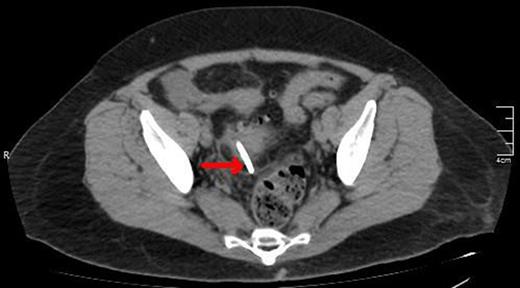

A CT view of the same patient showing the lower edge of the biliary stent perforating the sigmoid colon (red arrow).